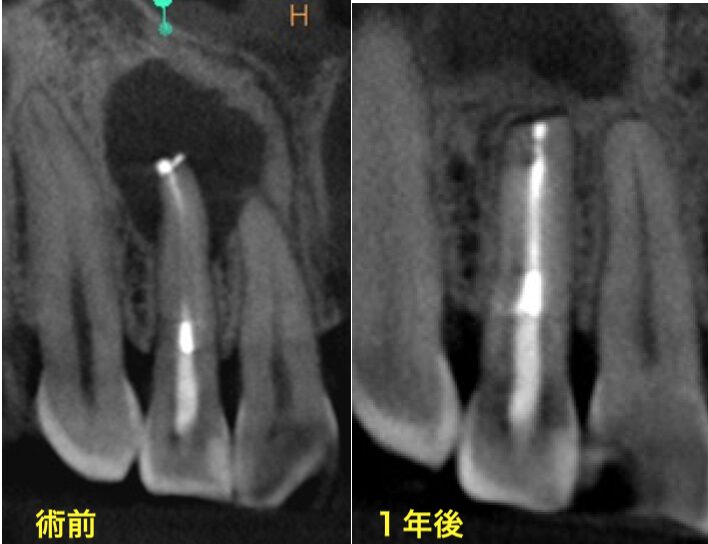

• 術前のCBCT画像、右上6の近心頬側根に大きな透過像(炎症の黒い影、赤矢印)があり、腫れの原因となっていることがわかる。未処置の根管、MB2(黄色矢印)は極度に石灰化していて根管のアウトラインも見られない。過去のラバーダム使用の自費の治療でもこういった部分が殺菌できないと病気を治すことは難しい。当院の再治療で石灰化根管の処置が可能かどうかは行ってみないとわからない、また上のケースのように殺菌ができても治らない場合もありえるため、より確実な方法として歯根端切除術を行うこととなりました。

• 術後1年の経過観察時のCBCT画像。治療前の炎症増は無くなり骨の再生が見られ経過良好です。石灰化MB2の部分に充填がなされていることがわかります(黄色矢印)。このように、感染除去を行って、しっかり封鎖をすることで根管治療を繰り返しても治らない難症例も治癒に導くことが可能です。